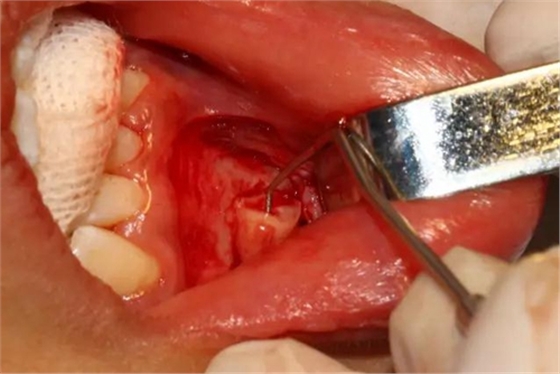

創(chuàng)口處理

創(chuàng)口內(nèi)置入膠質(zhì)銀明膠

關(guān)閉創(chuàng)口、對(duì)位縫合

取出的離體43